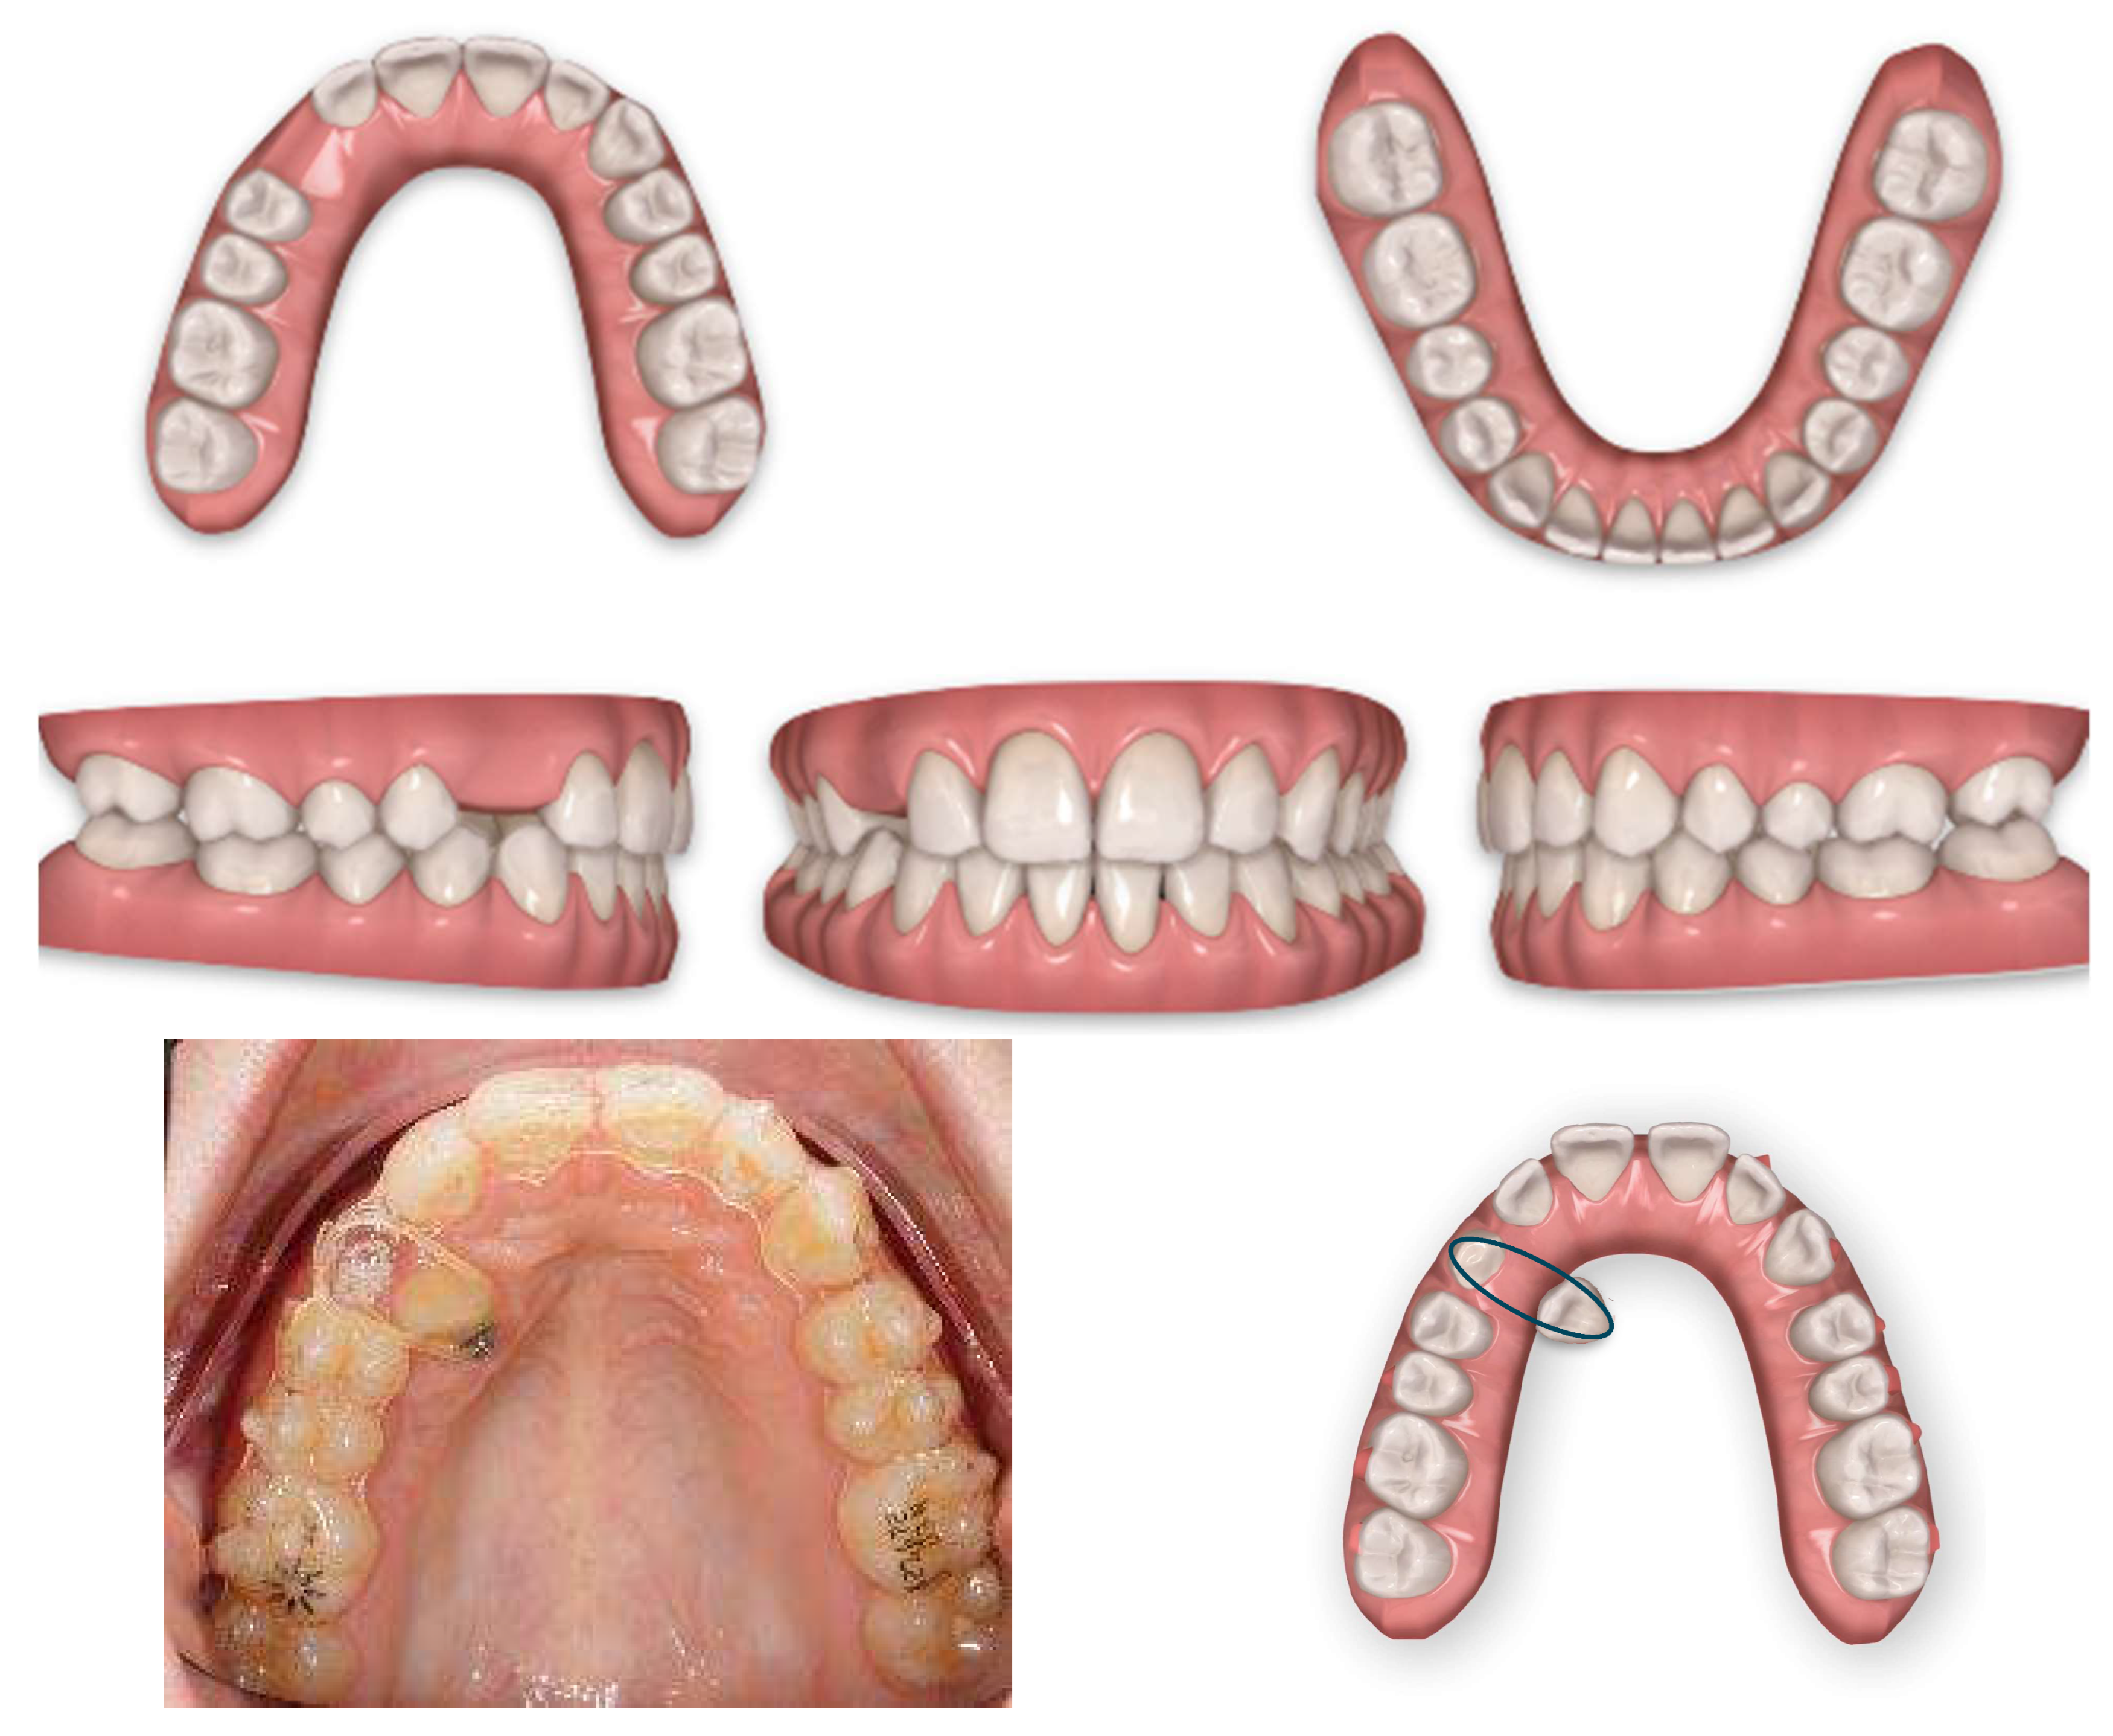

As for the palatally displaced canine, the cantilever spring was activated until the canine was visible and near the crest. Then, the deciduous canine was extracted and intraoral digital scans were taken by using the 3D scanner to start the orthodontic treatment (Figure 4).

Figure 4.

After 6 months of cantilever spring activation in extrusion and distalisation.

At the first Clincheck®, the use of an eruption compensator was planned in order to link the displaced canine to the aligner, through an elastic ligature, thus facilitating the desired movement. Bite ramps are usually placed in order to disocclude the upper and lower arches and increase the movement of the canine from the palatal to the vestibular side (Figure 5 and Figure 6).

Figure 5.

First Clincheck® and first set of aligners to create space, reach alignment and levelling of both arches. The use of elastics and button as auxiliaries to promote the movement of the impacted canine.

Figure 6.

Progress of treatment with mechanics of elastics.

Once the disimpacted canine was in a better position and near to the crest, intraoral impressions and a new series of pictures were taken (Figure 7).

Figure 7.

First refinement with the involvement of the 1.3 in the aligner and consequent alignment and levelling of both arches.

A horizontal rectangular attachment was placed on the buccal surface of the canine and a buccal root torque was applied to ensure the three-dimensional control of the tooth movement (Figure 8).

Figure 8.

Horizontal Rectangular gingival bevelled attachment to improve the fitting on the 1.3 and buccal root torque.